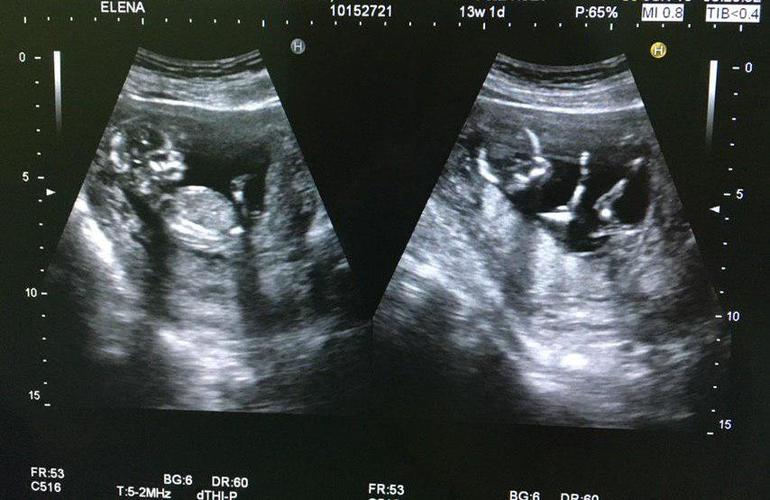

Пол малышаНу вот, сходила сегодня на узи. Срок: примерно 13недель и 5 дней. Думала что уж сегодня наверняка сделают предположение о поле малыша. Так узистка сказала что еще рано, и на следующем узи уж точно увидят. Но мне всё равно ужасно интересно кто же у меня там сидит))) Девченки, вот ниже снимки с видео, мне показалось что на первом снимке девочка, а на остальных вроде мальчик. А вы что видете?))))